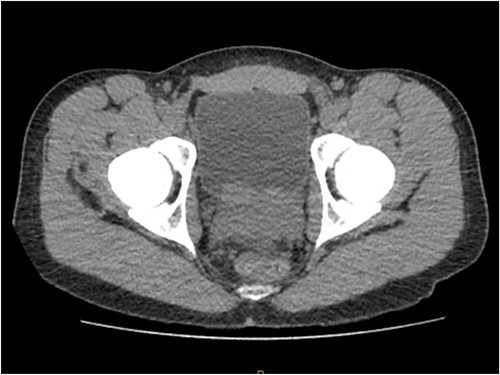

Patient was catheterised and subsequently underwent bilateral ureteric stenting. Cystoscopic views of the prostate was also abnormal and concerning for malignancy, so transperinal prostate biopsy was performed. Histology of this confirmed diffuse large B cell lymphoma. Renal function improved post ureteric stenting and patient was referred to haematology for management of DLBCL. Progress FDG PET scan (Fig. 4) 3 months post R-CHOP chemotherapy showed complete metabolic response with no avid residual lymphoma.

PET FDG scan post R-CHOP chemotherapy showing prostate with complete resolution from the disease.